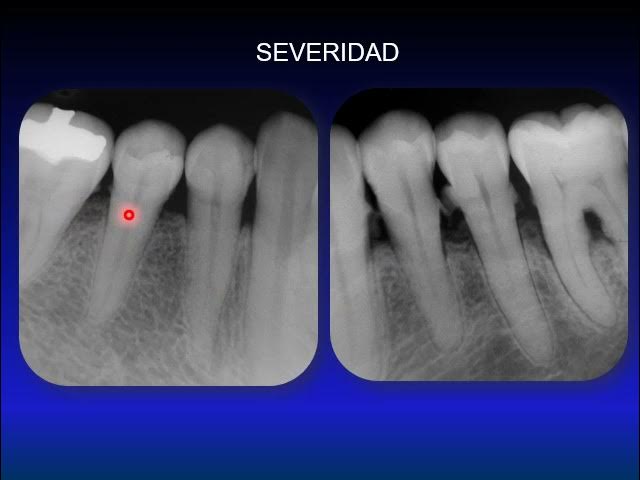

Signos Radiográficos de la Enfermedad Periodontal – Dento Metric | Radiología Dental, Oral y Maxilofacial

Manifestaciones radiográficas del bruxismo en pacientes adultos | Lazo-Nodarse | Archivo Médico Camagüey

Periodoncia – trauma oclusal Periodontics – occlusal trauma Periodontia - trauma occlusal